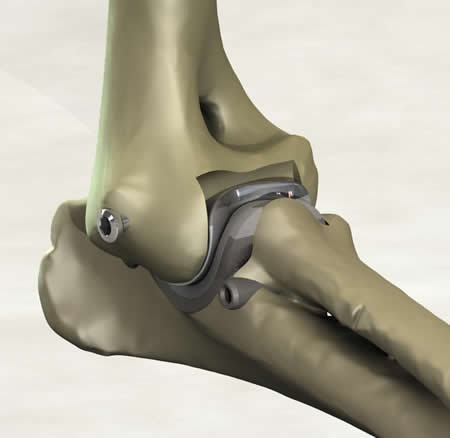

It is a minimally invasive resurfacing arthroplasty of the canine elbow.

I remember the day the mill and drill concept was developed and it just felt right. We had attempted bone preparation with saws and spine burrs, and we finally started talking about milling. Custom end mills were developed and the cuts were fast and accurate. We realized that drilling for implant attachment to bone, then milling, would allow preparation of both sides of the joint simultaneously without disarticulation. The collateral ligaments were preserved in their original length with no impingement through the range of motion. The cartridge concept soon followed, and I felt we were on the way. After implanting many cadavers with different SLA prototypes, our tenth prototype felt right in the cadaver. We tested for full range of motion with stability in extension and flexion.

What is novel about the concept?

Simultaneous preparation of both joint surfaces using the axis of rotation as the mill datum has not been done before. The other unique aspect of the patent is inserting both components of an arthroplasty together as a cartridge. These concepts potentially provide for improved alignment of the implants, reduced surgical trauma and reduced surgical time.